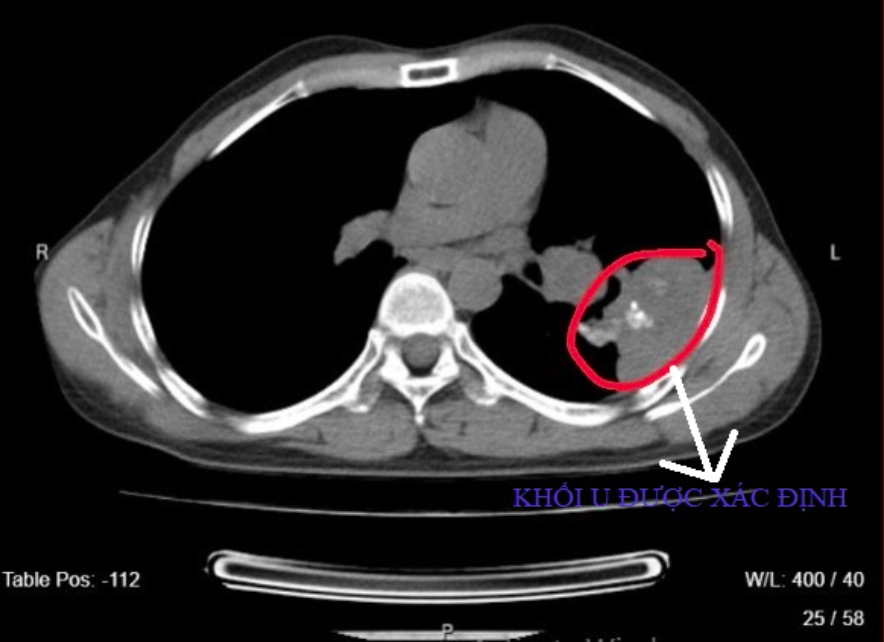

Trên hình ảnh CT-Scanner lồng ngực kết luận bệnh nhân có hình ảnh các khối, đám tổn thương tổ chức thùy trên hai phổi; hạch trung thất, nền cổ, khối vị trí tuyến lượng thận phải, dày màng phổi thùy bên trái; các đám xơ dày tổ chức kẽ đính phổi hai bên; tiêu xương cung sau xương sườn 5 bên trái.

Bác sĩ phát hiện khối u trong phổi bệnh nhân. Ảnh: BVCC.

"Bệnh nhân có tiền sử lao phổi đã điều trị cách đây 10 năm. Điều đáng quan tâm là chúng tôi đã phát hiện u phổi, hạch, và tiêu xương, bệnh nhân đau lan tỏa ngực, gầy sút cân, đó là những dữ liệu quan trọng định hướng nghi ngờ nguy cơ cao bị ung thư phổi, giới thiệu bệnh nhân lên tuyến trên để chẩn đoán chính xác", bác sĩ Tuấn nói.